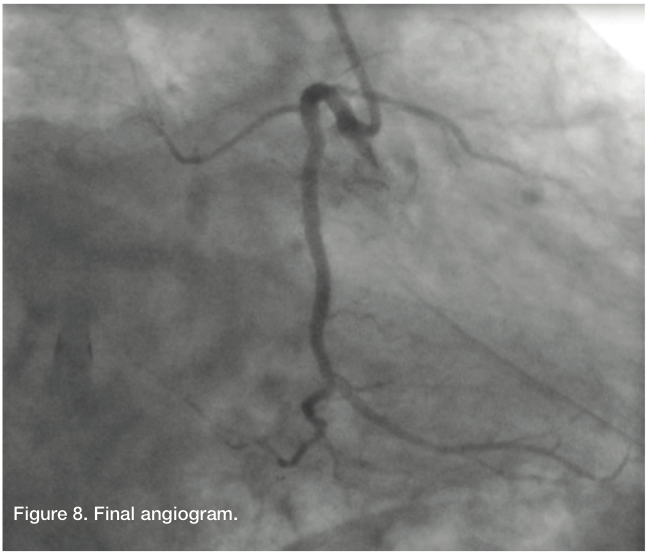

The patient’s angiographic finding demonstrated a degree of patency, a result of the previous retrograde balloon dilation of the RCA. We changed to an Amplatz right (AR) Mod guide catheter, because the AL 0.75 was engaging the dissection too deeply and would not allow us to steer our wire in the desired direction. Using a Fielder wire and a 1.25 mm balloon, we were able to cross, and advance the balloon and wire distally into the PDA and exchange out for an Iron Man support wire (Abbott Vascular). After removal of the 1.25 balloon (Medtronic), we predilated with a 2.0 x 15 Apex catheter (Boston Scientific). This was then followed by a 2.5 x 15mm AngioSculpt (Angioscore) to predilate the mid and distal RCA. Intravascular ultrasound (IVUS) (Volcano) showed that the vessel was actually about 3.0 mm in the distal and mid portion, with a dissection clearly noted in the proximal portion. The vessel was about 4.0 mm proximally. We took a 3.0 x 30 mm Resolute (Medtronic) drug-eluting stent and deployed it from the distal to mid RCA. The Resolute was overlapped with another 3.0 x 30 mm Resolute, and then a 3.5 x 26 mm Resolute, going all the way back to the proximal RCA, but not involving the ostium. All stents were post dilated with Quantum balloons at high pressure. Stent size and apposition was confirmed by IVUS. Final angiography revealed TIMI-3 flow without dissection, perforation, or embolization. The patient had an uncomplicated hospital course and was discharged home the next morning.